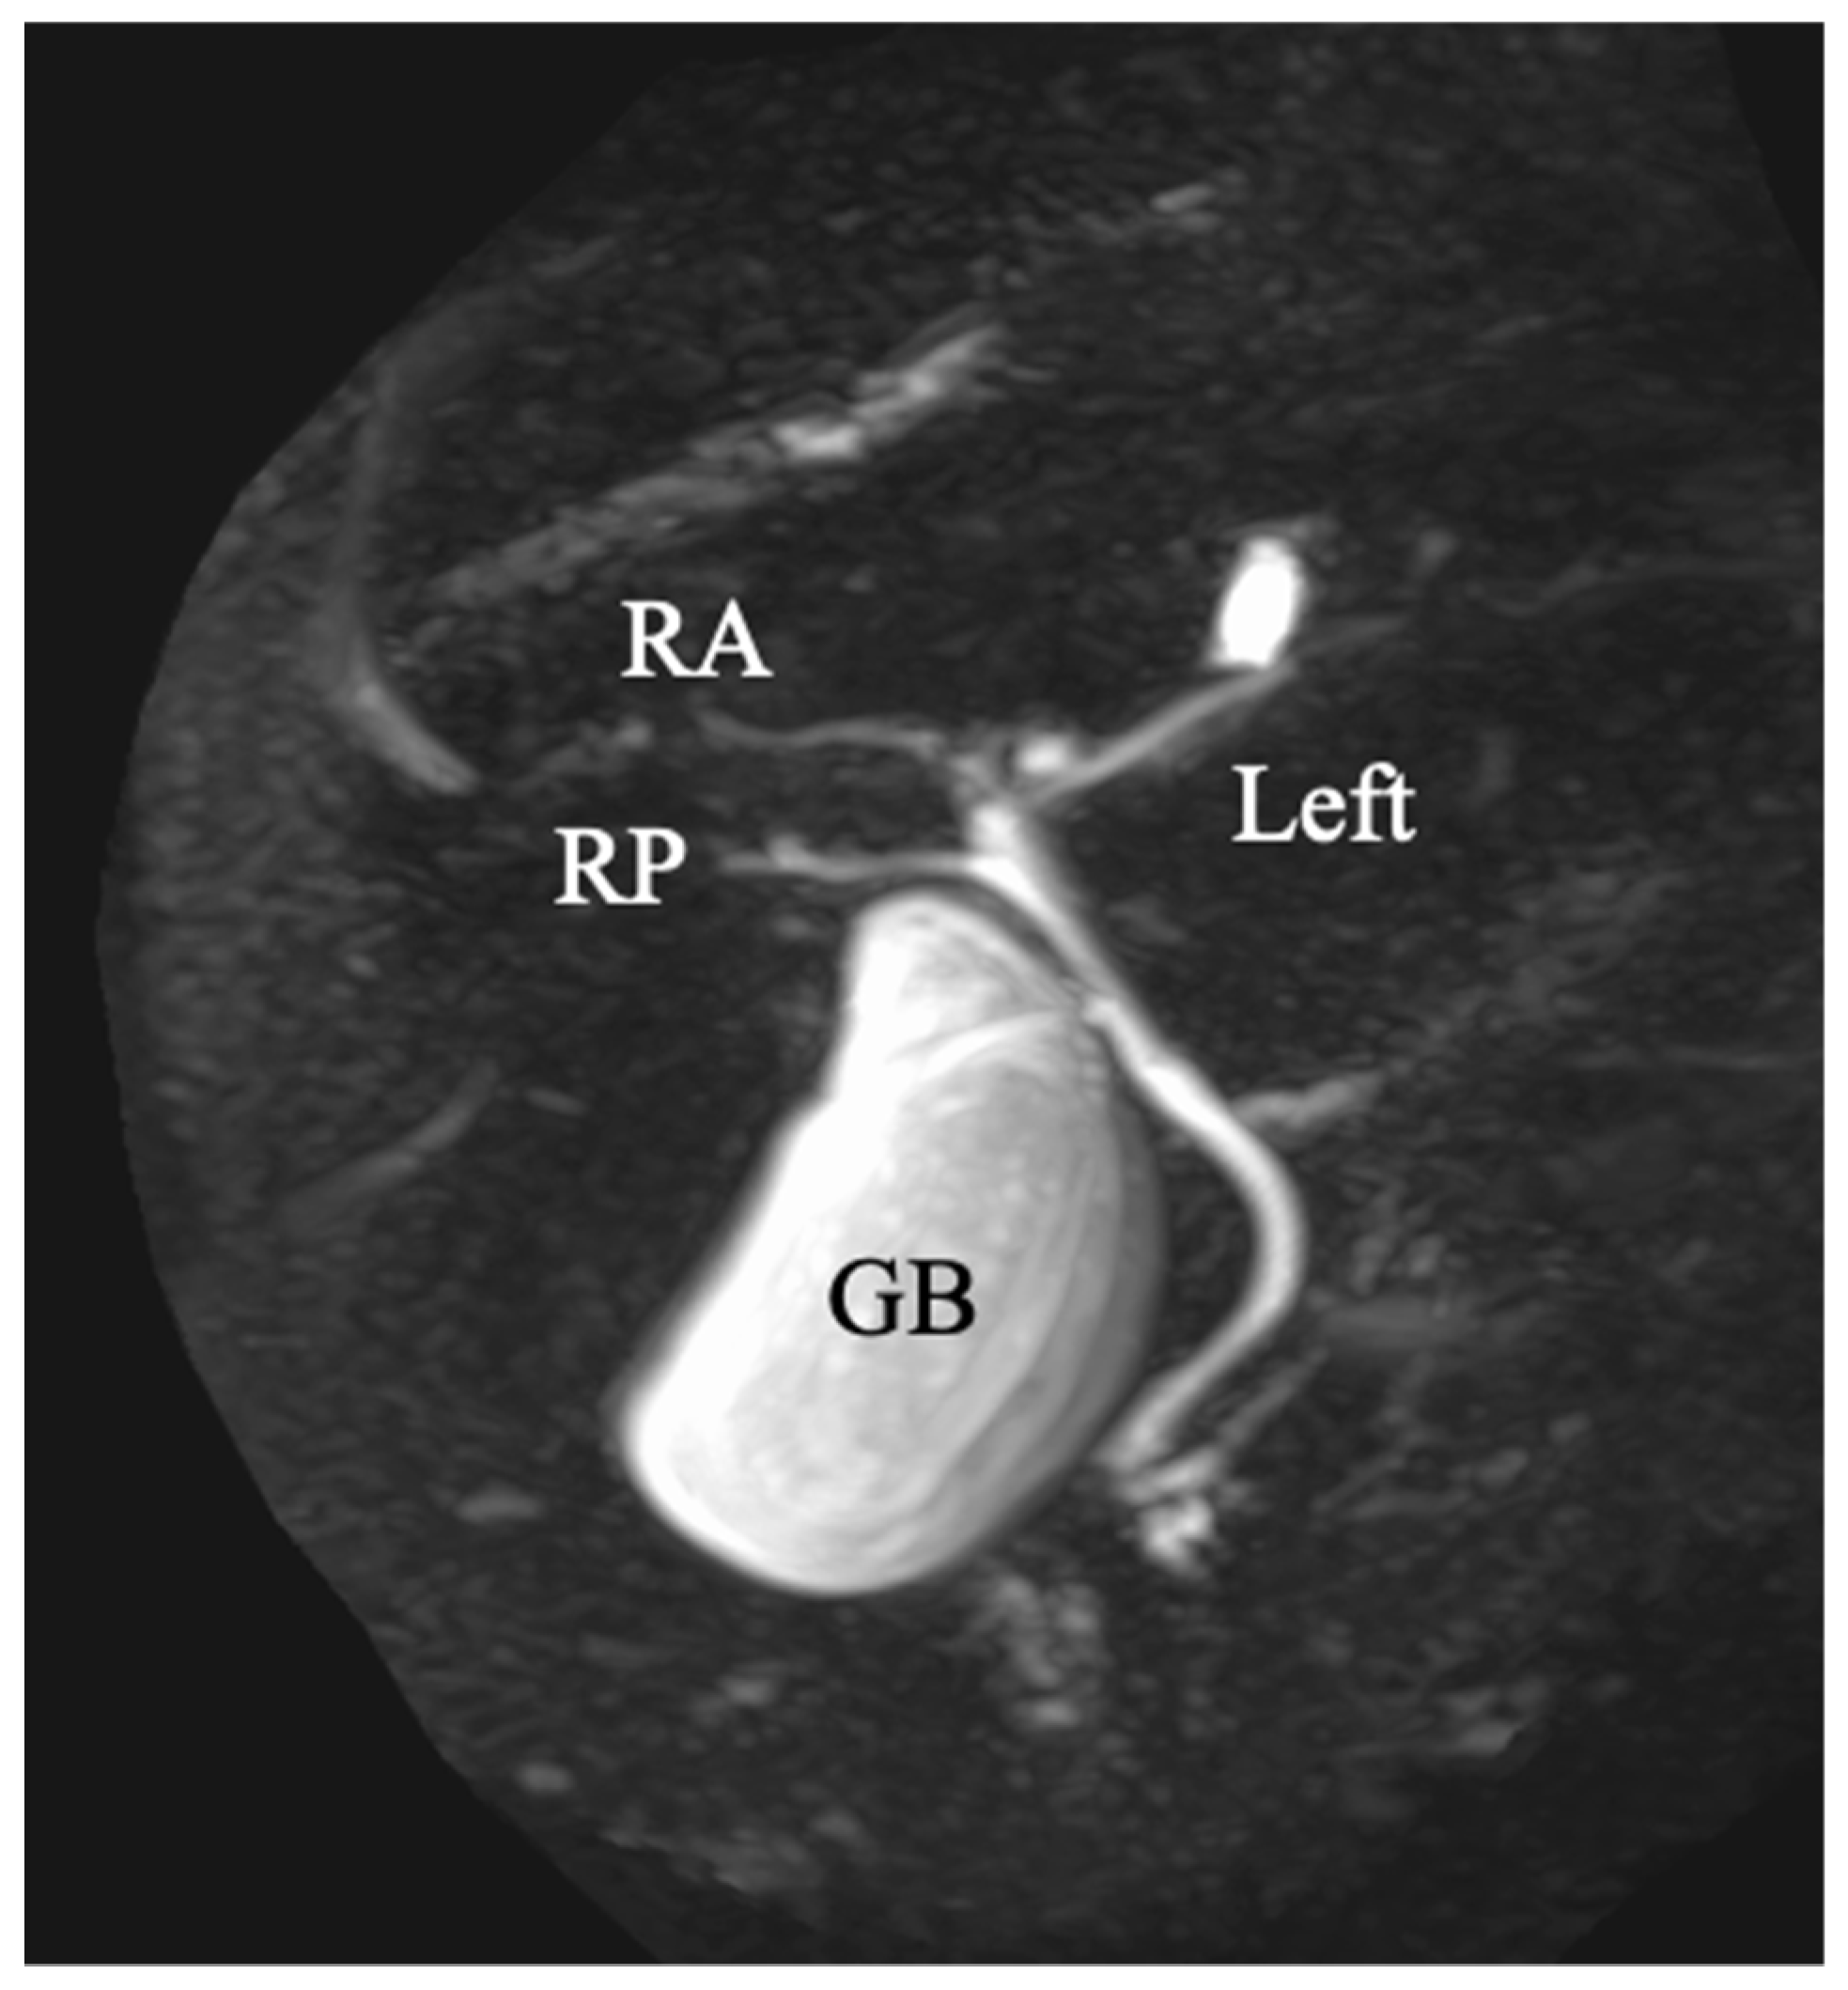

Figure 5. Magnetic resonance cholangiopancreatography revealed that the bile duct system was trifurcated into right posterior (RP), right anterior (RA) and left branches. GB indicates the gallbladder.

A 69-year-old man was referred for evaluation of a liver tumor detected on abdominal ultrasonography performed for nonalcoholic steatohepatitis follow-up. Blood testing showed elevations in concentrations of aspartate transaminase (56 U/L), alanine transaminase (51 U/L), and protein induced by vitamin K absence-II (224 mAU/mL). Other tumor markers and hepatitis virus markers were negative. The indocyanine green retention rate at 15 minutes was 15.2% and Child–Pugh score was 5 points (class A), suggesting good hepatic function. Computed tomography (CT) showed a 2.4 × 2.0 cm hypodense mass in the left lobe of the liver (S2/3/4b) which exhibited early arterial enhancement and washout (Figure 1). Hepatocellular carcinoma was highly suspected. In addition, the ligamentum teres was connected to the right anterior branch of the portal vein, and the gallbladder was located to its left, indicating RSLT (Figure 2). On magnetic resonance imaging, the mass was low signal intensity on T1-weighted images and high signal intensity on T2-weighted and diffusion-weighted images; contrasted imaging using gadolinium ethoxybenzyl diethylenetriamine penta-acetic acid revealed a perfusion defect in the mass in the liver phase (Figure 3). Three-dimensional CT (Synapse Vincent®︎; Fujifilm Medical, Tokyo, Japan) demonstrated right posterior, right anterior, and left branches of the portal vein. The left branch branched into P2 and P3 after two P4 branches separated. A right inferior hepatic vein and V8 were present (Figure 4). Magnetic resonance cholangiopancreatography revealed that the bile duct system was trifurcated into right posterior, right anterior branch, and left branches (Figure 5). After the pertinent anatomy was clarified and the preoperative evaluation was completed, we elected to perform laparoscopic extended lateral sectionectomy.